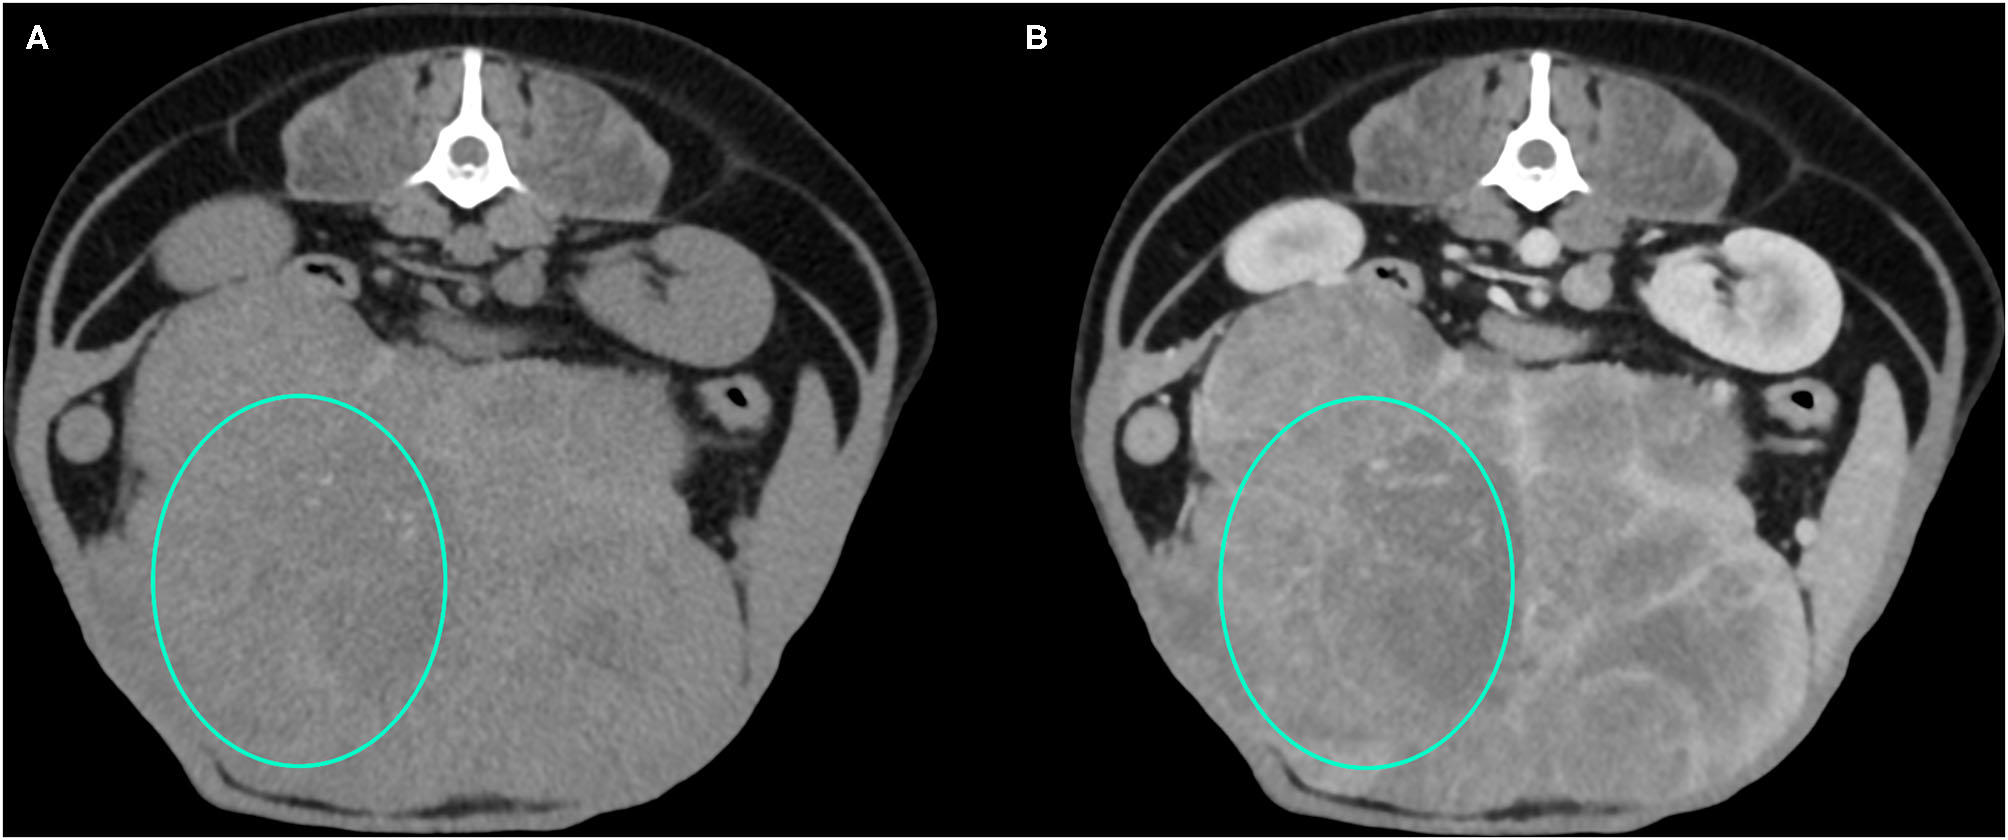

Figure 3

Example of an HCC showing hypoattenuation and hypoenhancement, diffuse contrast enhancement pattern, with heterogeneous distribution, well-defined margins, irregular surface, and cyst-like appearance. (A) image obtained from the pre-contrast scan; (B) image obtained from the delayed scan. A ROI is placed inside the lesion in both. Based on the developed decision tree this lesion was classified as HCC.